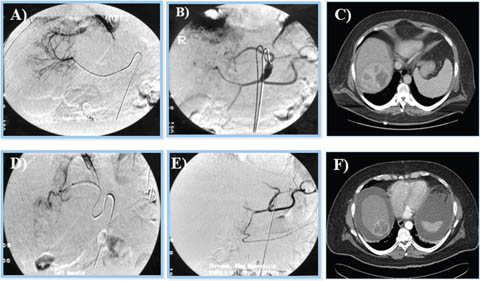

Fig 8

Figure 8. Ultrasound-guided percutaneous alcohol injection of hepatocellular carcinoma. A and B. Under image-guidance by US, administration of ethanol (97%) is performed into the tumor. C. Noting an enlarging hyperechoic signal. Although the procedure in well-trained hands is reliable and practical for large scale application, malignant recurrence rates are high.